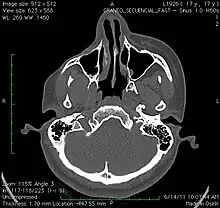

A 3D, soft tissue reconstruction of a CT scan of a 17-year-old girl with Parry Romberg syndrome. A 3D, soft tissue reconstruction of a CT scan of a 17-year-old girl with Parry Romberg syndrome.

CT scan3D bone reconstruction of a 17-year-old girl with Parry Romberg syndrome. CT scan3D bone reconstruction of a 17-year-old girl with Parry Romberg syndrome.